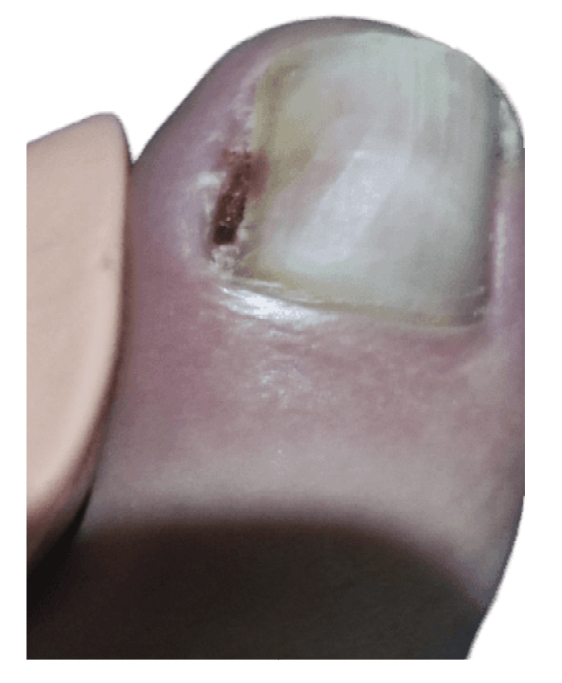

La paciente presenta inicialmente mejoría del dolor, aunque nunca termina de ceder completamente (Figura 4). Refiere recurrencia de la lesión ungueal lo que le lleva a consultar una segunda opinión a las 6 semanas de la intervención con otro podólogo. Este último con fecha 27 de diciembre (Figura 5) realiza cultivo bacteriano de la lesión, resultando negativo, y también valoración de la lesión mediante ecografía (sin informe). El 13 de enero la paciente es intervenida quirúrgicamente mediante técnica fenol-alcohol en el borde lateral del primer dedo del pie izquierdo (Figura 6).

Figura 4. Semanas 9-14. Recurrencia progresiva de la lesión tras resección parcial.

Figura 5. Semana 16. Cultivo bacteriano negativo y valoración por ecografía (no disponible).

Figura 6. Semana 18. Segunda intervención mediante matricectomía parcial con técnica fenol-alcohol.

En el transcurso de 3 semanas después de la tercera intervención, la paciente refiere recidiva de la lesión y de la sintomatología dolorosa (Figura 7). La paciente decide acudir a servicio de traumatología (febrero de 2023) donde se solicita la realización de resonancia magnética nuclear (T2FS y DPFATSAT). En ella, se aprecia masa ocupante en el tercio lateral del primer dedo con bordes bien definidos y afectación ósea (Figura 8) con el siguiente informe: “A nivel de la falange distal del primer dedo en la región ungueal impresiona solución de continuidad cutánea con colección heterogénea, densa de 15 mm × 14 mm que se ubica en la región lateral de partes blandas parafalángicas, remodela el hueso y se pone en contacto con el tendón flexor, pudiera corresponderse con absceso/colección flemonosa postquirúrgica. Impresiona algo de edema óseo en falange distal sin descartar completamente incipiente osteomielitis. A confrontar con antecedentes y protocolo quirúrgico realizado”.

Figura 7. Semana 21. Recidiva de la lesión tras fenolización.